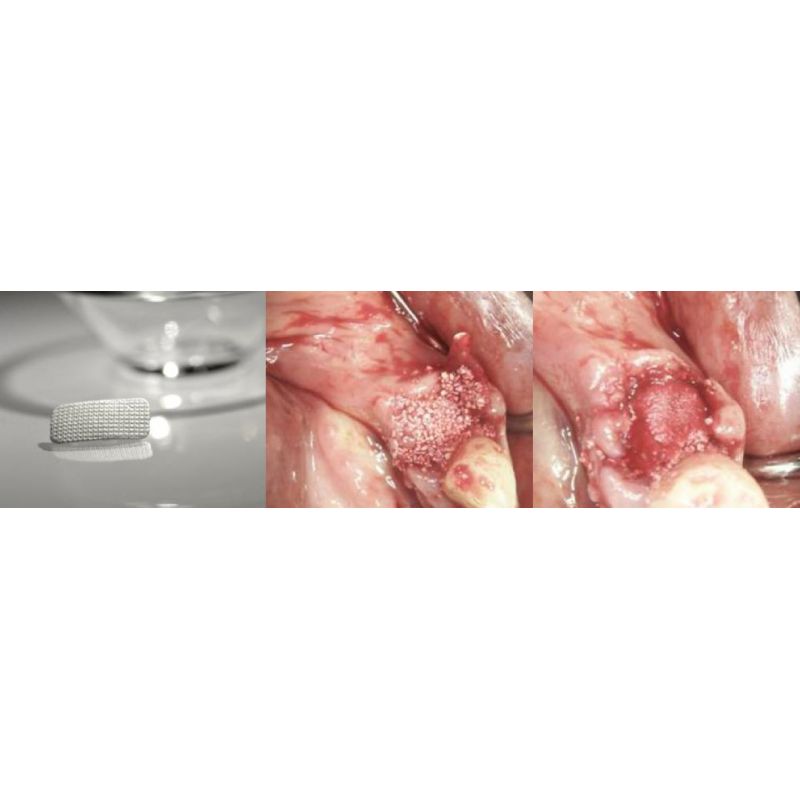

Membrana colagen SinossMem AlveolarRepair, 10 x 20 mm

Tehnica simplificata de reparare a alveolei pentru defecte faciale aparute in urma extractiilor si prezervarea crestei alveolare.

SinossMem AlveolarRepair este o membrana de colagen resorbabila nativa, dezvoltata pentru diferite tipuri reparatii ale alveolelor atunci când avem suficient tesut moale, dar tablia osoasa vestibulara este compromisa in urma extractiei dintilor.

Vindecarea osului si rezultatul estetic arata ca reconstructia imediata a unui defect osos extensiv cu pierderea completa a lamelei osoase este o optiune de terapie de succes.

Datorita marimii sale, SinossMem AlveolarRepair acopera doar parti ale peretilor. Astfel, impiedica migrarea materialului grefier osos granular si infiltrarea tesutului moale în defectul osos. Permite celulelor osoase de pe pereti sa creasca in zona afectata si sa incurajeze formarea de tesut osos nou datorita acoperirii mici.